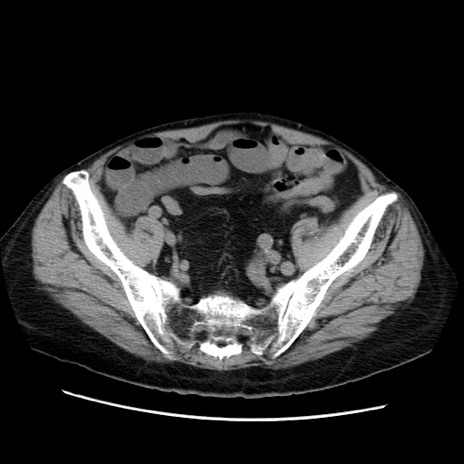

冠状断像

【症例】70歳代男性

【主訴】腹痛

【現病歴】肝硬変・肝細胞癌にてかかりつけの方。約9時間前に食後より腹痛出現。症状が徐々に増悪し、嘔吐出現したため来院。

【既往歴】肝硬変、肝細胞癌(RFA、TACE後)

【身体所見】意識清明、表情苦悶様、BT 36℃、BP 129/78mmHg、P 88bpm、SpO2 97%(RA)、右上腹部から心窩部にかけて圧痛あり、反跳痛なし、筋性防御あり。

【データ】WBC 5800、CRP 0.16